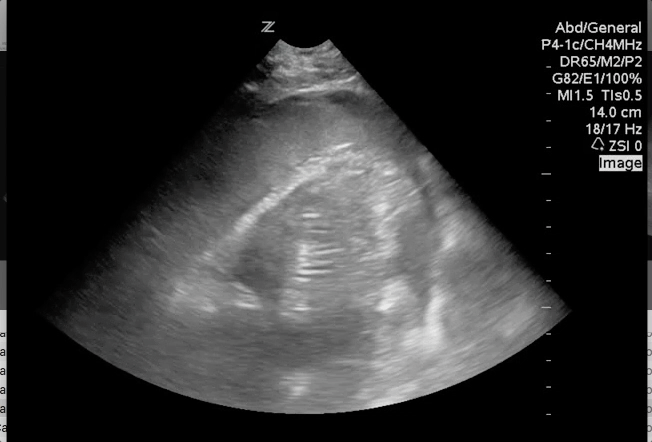

Sonography for Hypotension and Cardiac Arrest Continued. This + hands on training is how we #meded students into residents. #POCUS #foamus #foamed

Previous Previous post: Sonography for Hypotension and Cardiac Arrest Part 1. This + hands on training is how we #meded as we transition students to residents. #POCUS #foamus #foamed